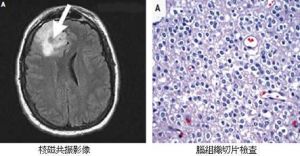

3.膠質瘤:神經膠質瘤來自神經系統支持組織,屬外胚葉腫瘤。膠質瘤按組織發生原則分為星形細胞瘤、成星形細胞瘤、成髓細胞瘤、少枝膠質細胞瘤、室管膜瘤、松果體瘤、神經上皮瘤。近年來根據膠質瘤的惡性程度分為Ⅰ-Ⅳ級,級別序數愈高,其惡性程度愈大,即瘤細胞分化較好、無核分裂及血管增生者為Ⅰ級;有25%-50%惡性細胞為Ⅱ級;50%-75%為Ⅲ級;75%-100%為Ⅳ級。惡性度高者瘤內常有壞死與出血,血管豐富,血管外層及內皮細胞均有明顯增生。

根據目前來看不像是腦瘤還像是腦出血。建議做強化核磁。針對病因治療。腦瘤不遺傳。生活中的常見病症(一)